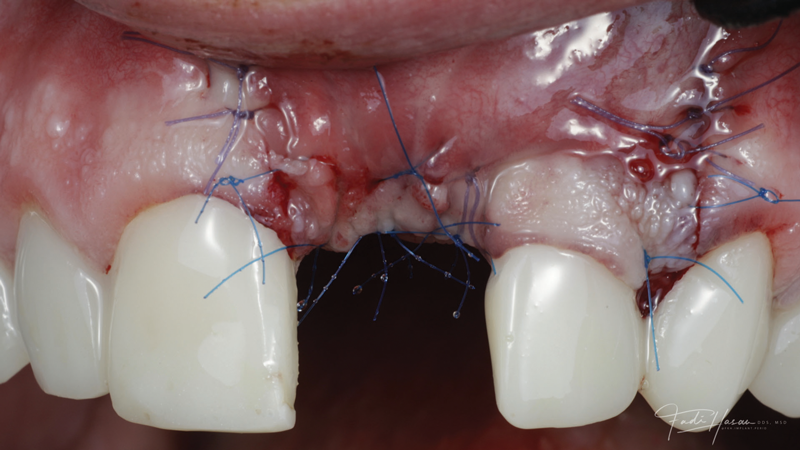

(8.) The flap was coronally positioned and sutured into place.

Figure 8

The patient in this case had undergone implant therapy at the site of tooth No. 9 and was restored with a cement-retained restoration more than 5 years prior. At presentation, the site demonstrated a peri-implant soft-tissue dehiscence that extended approximately 3-mm apical to the gingival margin of tooth No. 8. Thin and erythematous marginal tissue was evident at the zenith (Figure 2). The crown was removed, and a partial thickness flap was reflected using a papilla-sparing incision design. This revealed that the implant was positioned too far facially and that its body was visible through a very thin layer of bone (Figure 3 and Figure 4). The first objective of treatment was to minimize the facial extent of the emerging abutment and crown. To accomplish this, the facially positioned abutment and implant crown margin were both recontoured. The second treatment objective was to provide additional supracrestal soft tissue that would more adequately maintain the peri-implant margin. The tuberosity was selected as a donor site due to its dense, high-quality connective tissue, low propensity for shrinkage, and association with minimal patient discomfort. Once the graft was secured (Figure 5 through Figure 7), the flap was coronally positioned (Figure 8). After a healing period of 2 weeks, the margin of tooth No. 9 exhibited an ideal position in relation to its contralateral counterpart and demonstrated increased soft tissue thickness (Figure 9). Three months postoperatively, further healing had improved the esthetics and the position of the margin had been maintained (Figure 10).